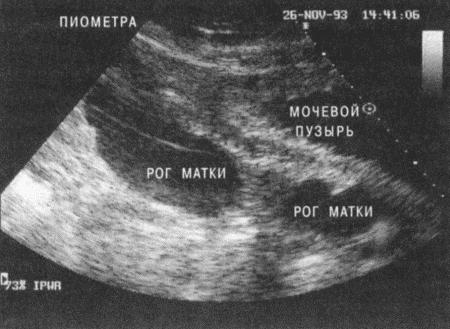

Фиг. 4.18.

Ультразвуковое сканирование матки при пиометре (с любезного разрешения профессора Jake Boyd)

Другой метод, позволяющий получить изображение увеличенных и заполненных жидкостью рогов матки, — ультразвуковое сканирование. Жидкость в норме анэхогенна (фиг. 4.18), хотя может содержать хлопья. Патологию дифференцируют от беременности по отсутствию костных тканей зародышей, характеру жидкости и размеру затемнений. Дополнительное преимущество ультразвукового сканирования состоит в том, что седация необязательна и частый мониторинг не представляет опасности для пациента.